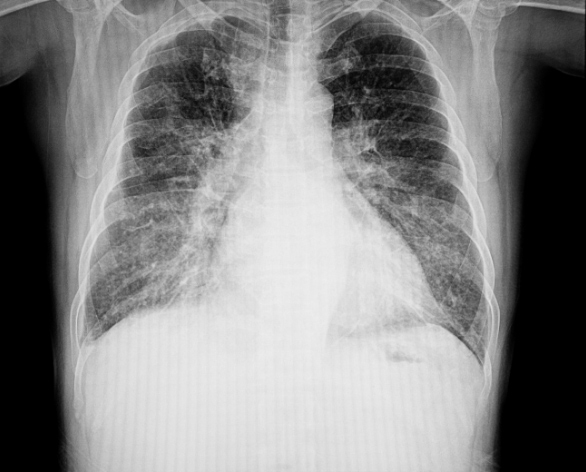

Παθήσεις του μεσοθωράκιου